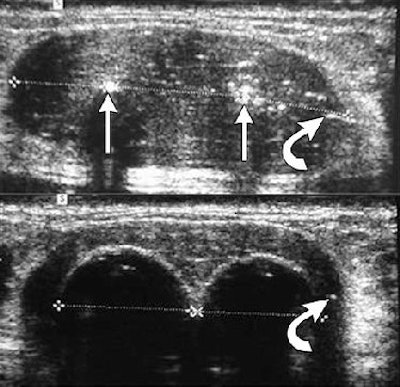

![]() |

| Ultrasound images during cryoablation showing an ice-ball formation with a cryoprobe through the center of fibroadenoma. Above, longitudinal axis; below, transverse axis. Images courtesy of Dr. Dennis R. Holmes, breast surgeon and director of new technology development, University of Southern California/Norris Comprehensive Cancer Center and Hospital, and chief, breast service, LAC+USC Medical Center, Los Angeles. |